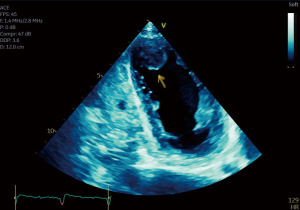

About 2 months later, she presented with left lower extremity pain, skin discoloration, subacute malaise, and weakness. Physical examination revealed dry, flaky skin, cool extremities with pitting edema, and blisters on both feet. Abdominal CT angiography showed extensive atherosclerotic disease and clots throughout the abdominal aorta and major branches, as well as LV, aortic, and pulmonary emboli. Repeat TTE demonstrated severely decreased LV function and a large apical LV thrombus (Figure 4, Video 2). Critical limb ischemia was diagnosed, and the patient was started on a heparin infusion. Surgical intervention was deemed high risk, and she was discharged on oral anticoagulation therapy. A repeat TTE performed approximately 1 year later showed LVEF recovery to 50–55%, supporting the role of early corticosteroid intervention and guideline-directed medical therapy (GDMT) in improving cardiac function. Pembrolizumab was permanently discontinued following the episode of immune-mediated myocarditis. No further systemic antitumor therapy was initiated thereafter. On serial imaging, the patient has remained in radiographic remission without evidence of disease progression for approximately 6 months following discontinuation.

While pembrolizumab-related myocarditis is documented in the literature, severe cardiomyopathy and heart failure are rarely reported. Prior cases of pembrolizumab-induced myocarditis exist (14,15), but data on severe nonischemic cardiomyopathy and subsequent LV apical thrombus are scarce. Our patient’s condition was complicated by systolic heart failure with EF 10–15% and subsequent LV thrombus and PE. Although pembrolizumab has been reported to be associated with acute thrombosis and PE (16), it remains unclear whether it increases the risk of LV thrombus formation independent of existing predisposing factors like cancer and atrial fibrillation. Additionally, it’s unknown if pembrolizumab-induced cardiomyopathy carries a higher risk of LV thrombus formation compared to other cardiomyopathies. Further research is needed to clarify the relationship between pembrolizumab and LV thrombus formation, along with the underlying pathophysiological mechanisms.